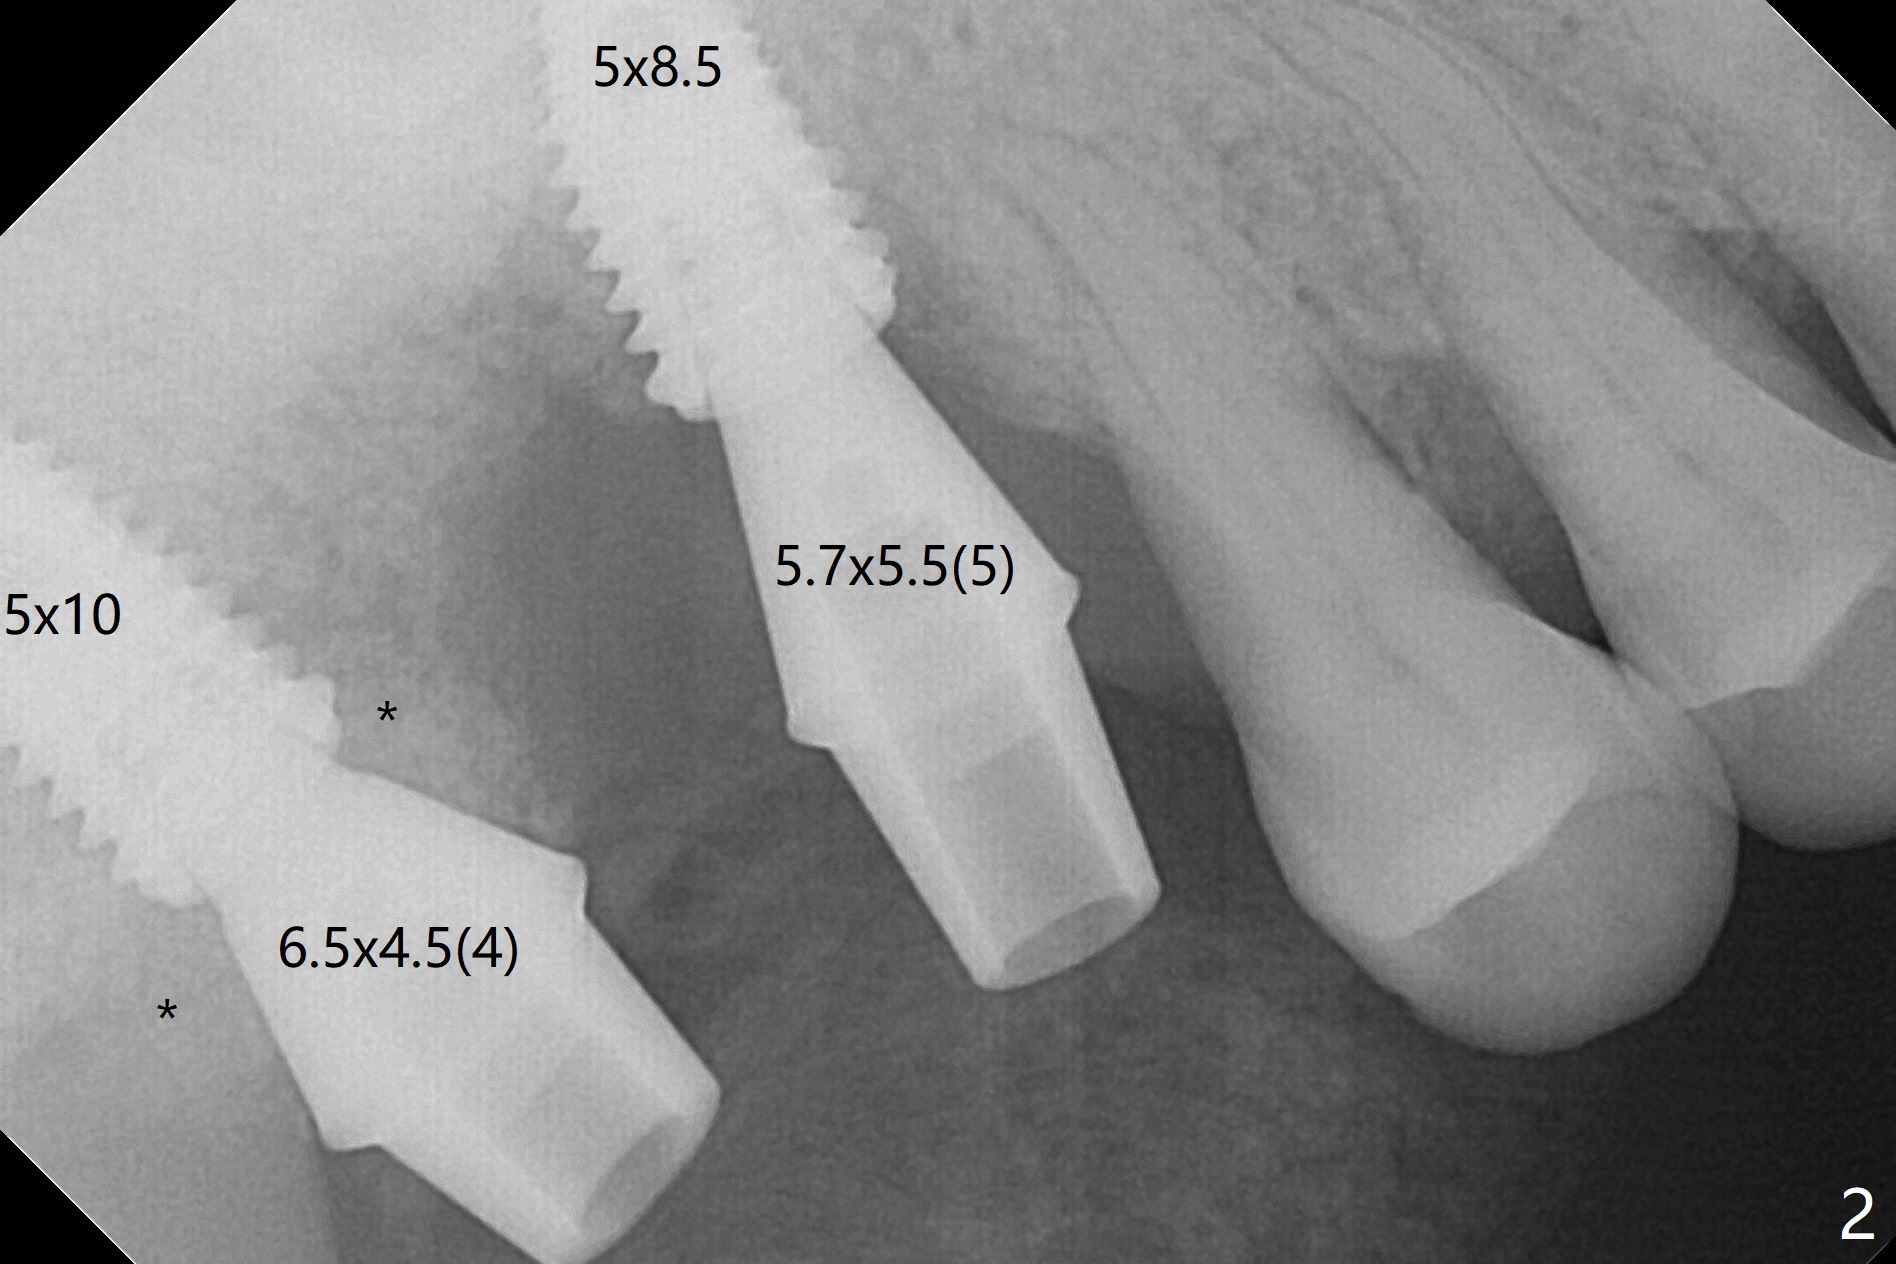

After use of 2.2 mm IS drill, DIO parallel pins are unstable at #2 and 3, partially due to shallow osteotomy. PA is not taken with parallel pins. When dummy implants are placed, the axis at #3 is noted; but instead of moving the apical end of the osteotomy distal (Fig.1 red line), the coronal end is moved mesial. By the time definitive implants and abutments are placed, the axis of #3 is parallel to that of #4, but close to each other (Fig.2,3). Orthogonal panoramic X-ray shows that they are critically close (Fig.4). If PA were taken with parallel pins after initial osteotomy, correction would be easy. The patient is doing fine postop without pain or nasal hemorrhage. There is no thread exposure 11 months postop (Fig.5). The abutment screw at #3 is retightened 7.5 months post cementation (Fig.6 (poor crown/implant ratio)).